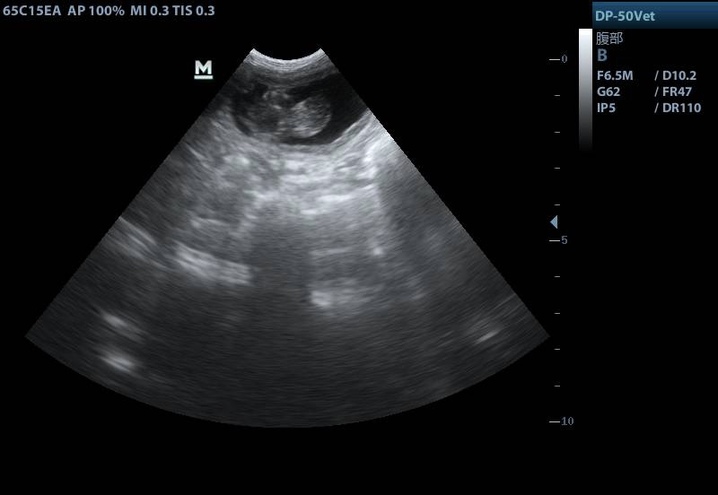

代孕母猫妊娠期间的B超图像。青岛农业大学供图